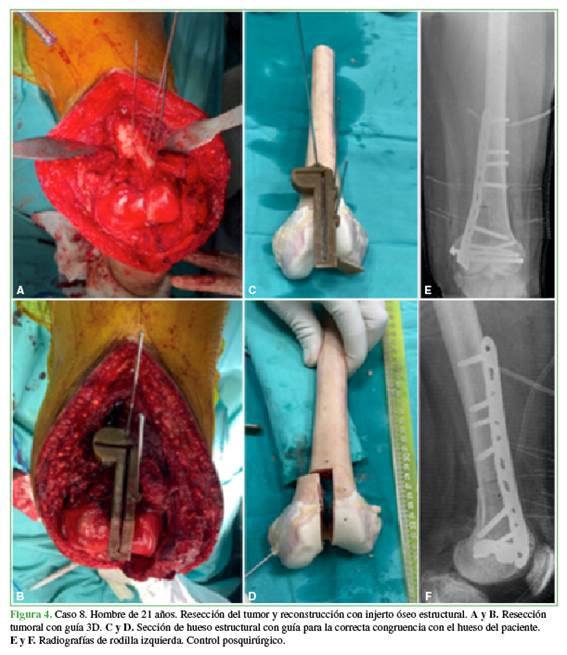

Se realizó la planificación digital en todos los pacientes utilizando los programas disponibles principalmente para mediciones y determinación de márgenes oncológicos, ángulos de osteotomía, cuantificación del volumen de injerto requerido o stock óseo disponible para la colocación de implantes. Los procedimientos quirúrgicos se desarrollaron según lo planificado y con los biomodelos impresos. No fue necesario ningún procedimiento intraquirúrgico adicional a los planificados. En los pacientes con enfermedad tumoral y aloinjerto, el plan quirúrgico inicial se modificó luego de la disponibilidad de los biomodelos; estas modificaciones consistieron principalmente en la localización de los planos de resección (Figura 4). En casos de reconstrucción con aloinjerto, fue posible la conformación de dos equipos quirúrgicos simultáneos, uno a cargo de la resección oncológica y otro, del procesamiento del injerto de banco; ocurrió algo similar en el caso del espaciador de cemento a medida, donde un equipo estuvo a cargo de la limpieza, mientras otro conformaba el espaciador.

El diseño de guías de corte para resección de tumores en la pelvis fue analizado en un estudio experimental con 10 especímenes cadavéricos y se halló un error medio no estadísticamente significativo comparado con las cirugías navegadas.8 Además, reduce la curva de aprendizaje y la experiencia acumulada para lograr resultados similares entre cirujanos jóvenes y profesionales especializados.7 En nuestros pacientes, las guías permitieron lograr una correcta reproducibilidad entre lo planificado y lo ejecutado en el quirófano. Otro uso para las guías de corte fue lograr una adecuada congruencia en las reconstrucciones con aloinjerto, en pacientes con resecciones oncológicas, de acuerdo con los principios de las técnicas quirúrgicas, para maximizar las posibilidades de integración.8,9